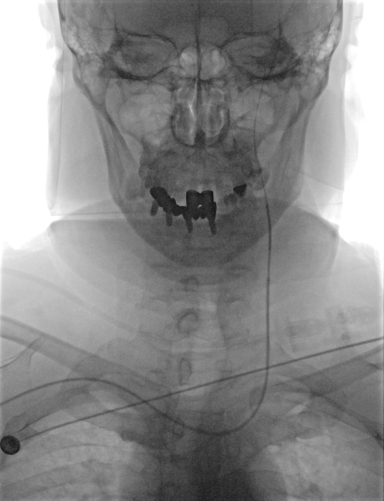

术前检查

颅脑CT无出血及新发梗死灶。